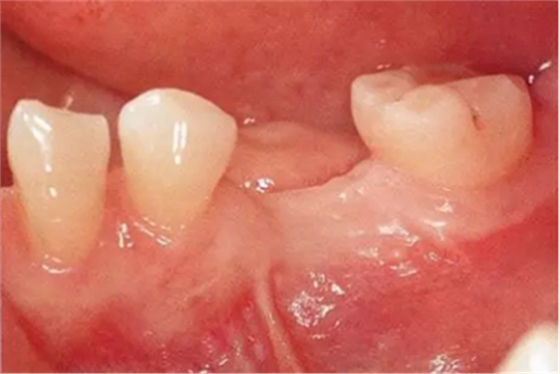

▲圖9-1

頰側和牙槽嵴幾乎沒有角化齦(Type3-Class1)

▲圖9-2,3

圖9-2 全損牙槽嵴的頂部,將牙齦移植片固定在頰側方向。待牙齦愈合后植入種植體。

圖9-3 牙齦愈合后的狀態(tài)。缺損牙槽嵴和頰側均獲得了角化齦。

▲圖9-4

佩戴最終修復體時的狀態(tài)。